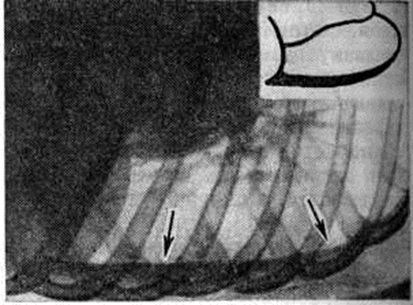

Выпотной Плеврит с накоплением серозного и серозно-фибринозного выпота является самым частым вариантом туберкулёзного Плеврит Наблюдается при образовании множественных туберкулёзных бугорков на плевре, иногда сливающихся между собой в более крупные очаги, а также при казеозном некрозе отдельных крупных очагов. Однако в этом случае в клеточном составе выпота преобладают нейтрофилы. При более распространённом казеозном некрозе плевры выпот становится серозно-гнойным, а при обширных поражениях — гнойным. В случае прорыва в плевральную полость субплеврально расположенных туберкулёзных очагов и каверн возникает обширный казеозный некроз плевры, сопровождающийся также экссудативной воспалительной реакцией плевры и накоплением выпота, нередко гнойного. При гнойном Плеврит (эмпиеме плевры) гнойный выпот скапливается преимущественно в нижних отделах плевральной полости. Гнойный Плеврит пневмококковой природы обычно сочетается с фибринозным выпотом и поэтому характеризуется скоплением гноя среди фибринозных «камер», располагающихся в нижних отделах плевральной полости. Стафилококки и стрептококки вызывают чисто гнойный Плеврит со скоплением жёлто-зелёного сливкообразного гноя в первом случае и жидкого серого — во втором. Плевра при этом тусклая, покрыта гноем, иногда некротизирована, пронизана колониями микробов. Мезотелий слущен, все слои плевры инфильтрированы нейтрофильными гранулоцитами, макрофагами, границы слоёв стёрты. При наличии в плевре тромбоваскулитов гнойная инфильтрация с висцеральной плевры может распространяться на лёгкое — так называемый кортикоплеврит, а с париетальной — на межмышечную клетчатку грудной стенки. Гнилостный Плеврит является следствием проникновения в плевру гнилостных микробов из очагов гангренозного распада лёгкого, осложнившего пневмонию, инфаркт или рак лёгкого. Выпот при этом буровато-серый с гнилостным запахом, иногда процесс течёт с образованием газа. При неэффективном лечении эмпиема приобретает хронический течение: грануляции рубцуются, лимфатических, коллекторы плевры облитерируются, развивается сетчатый лимфогенный пневмосклероз (смотри полный свод знаний). При этом спавшееся лёгкое фиксируется, фибринозные наложения на его поверхности, а также на париетальной плевре подвергаются организации; в результате этого создаётся ригидная остаточная плевральная полость, в которой сохраняется гнойный процесс, приобретающий хронический характер, формируются бронхоплевральные и плевро-кожные свищи. На фоне формирования спаек, свободный выпот в плевральной полости осумковывается, сгущается, иногда превращаясь в крошковатую массу, содержащую кристаллы холестерина (псевдохилёзный Плеврит) и известь. Иногда при обширной гнойной деструкции лёгочной ткани висцеральная плевра пронизана множеством бронхиальных свищей (смотри полный свод знаний), так называемый «решетчатое лёгкое». Функциональные нарушения, возникающие при плевритеФункциональные нарушения, возникающие при плеврите. Болевая реакция, возникающая при сухом Плеврит в результате трения воспалённых и покрытых фибринозными наложениями частей висцеральной и париетальной плевры и раздражения рецепторов, которыми обильно снабжена париетальная плевра, ведёт к ограничению глубины и, соответственно, увеличению частоты дыхания (смотри полный свод знаний). При накоплении выпота возникают нарушения, связанные с коллабированием и компрессионным ателектазом лёгкого, а также смещением средостения в здоровую сторону. При умеренном количестве выпота возникает ограничение лёгочной вентиляции (смотри полный свод знаний), а компрессионный коллапс части альвеол может способствовать возникновению умеренной гипоксемии за счёт изменения соотношения между лёгочной вентиляцией и кровотоком. Смещение средостения при большом количестве выпота ведёт к ограничению вентиляции второго лёгкого, нарастанию дыхательной недостаточности (смотри полный свод знаний) и расстройству кровообращения (смотри полный свод знаний) в результате смещения сердца, нарушения притока к нему крови вследствие общего повышения внутригрудного давления, перегиба полых вен, что может привести к гибели больного. При гнойном Плеврит интоксикация, обусловленная всасыванием обширной поверхностью плевры микробных токсинов и продуктов распада белка (гнойно-резорбтивная лихорадка по И. В. Давыдовскому, 1954), ведёт к истощению больного, массивной потере белка (гнойно-резорбтивное истощение), изменениям со стороны паренхиматозных органов, в первую очередь почек — токсический нефрит, амилоидоз (смотри полный свод знаний Гнойно-резорбтивная лихорадка). Клиническая картинаКлиническая картина при Плеврит складывается из проявлений основного заболевания, осложнившегося Плеврит, проявлений собственно Плеврит, а также расстройств со стороны жизненно важных органов и систем, вызываемых Плеврит В клинике Плеврит различного происхождения выделяют синдром сухого (фибринозного) Плеврит, синдром выпотного негнойного Плеврит и синдром гнойного Плеврит (эмпиема плевры). В динамике заболевания эти синдромы могут наблюдаться изолированно или же переходить один в другой. Сухой плеврит является выражением реакции плевры на неспецифический воспалительный процесс в лёгочной паренхиме (пневмонию, абсцесс лёгкого), и его клинические, проявления обычно дополняют симптоматику этих заболеваний. В других случаях сухой Плеврит развивается как бы изолированно, без отчётливых изменений в лёгком, например, в результате переохлаждения. В этих случаях причиной возникновения фибринозного Плеврит может являться реакция плевры, сенсибилизированной к туберкулёзному антигену, который выделяется из очагов инфекции, локализующихся в бронхолёгочных лимфатических, узлах или в лёгочной ткани и клинически не проявляющихся. Сухой Плеврит обычно протекает остро или подостро. Основной жалобой больных является острая боль в соответствующей половине грудной клетки, связанная с дыханием. Боль локализуется в зоне появления фибринозных наложений и наиболее интенсивна в задненижних отделах грудной клетки, где взаимная подвижность висцеральной и париетальной плевры максимальна. Боль усиливается при глубоком вдохе, а также при наклоне туловища в противоположную сторону (симптом Шепельманна). Для уменьшения болевых ощущений больные стремятся дышать поверхностно или же принимают вынужденное положение в постели на больном боку, иммобилизируя таким образом поражённую половину грудной клетки. Общее состояние больных обычно остаётся удовлетворительным, если сухой Плеврит не сопутствует тяжёлым изменениям в лёгких. Температура достигает субфебрильных цифр. Дыхание поверхностное, учащённое, экскурсии грудной клетки уменьшены на стороне поражения. При пальпации грудной стенки на больной стороне, особенно у худощавых больных, можно определить характерную крепитацию, связанную с дыханием. При верхушечных Плеврит иногда выявляется умеренная болезненность трапециевидных мышц (симптом Штернберга) и мышц груди (симптом Поттенджера); может возникнуть триада Горнера (анофтальм, псевдоптоз, миоз) вследствие вовлечения в воспалительный и рубцовый процесс веточек шейно-симпатического сплетения (смотри полный свод знаний Бернара — Горнера синдром); при поражении плечевого сплетения могут появиться признаки плексита (смотри полный свод знаний). При парамедиастинальной локализации Плеврит и развитии слипчивого медиастинита (смотри, полный свод знаний) возможно вовлечение в спаечный процесс ветвей блуждающего нерва, что ведёт к возникновению сердцебиений, иногда к нарушению моторной и секреторной функции желудка. Главным и в большинстве случаев единственным аускультативным симптомом сухого Плеврит является шум трения плевры над областью фибринозных наложений. Иногда шум трения плевры бывает слышен даже на расстоянии (симптом Щукарёва). При исследовании крови может наблюдаться ускорение РОЭ и небольшой лейкоцитоз. Диагностические трудности могут встретиться при диафрагмальных сухих Плеврит, которые нередко сопровождают базальные пневмонии или же воспалительные процессы в органах верхнего этажа брюшной полости (в поддиафрагмальном пространстве). Шум трения плевры при этом обычно отсутствует, болевые ощущения могут иррадиировать по диафрагмальному нерву вверх, в область шеи, а по нижним межрёберным нервам в область живота, при этом нередко выявляется ригидность мышц живота на стороне поражения. Иногда возникает болезненная икота, боль при глотании. При пальпации могут выявляться болезненные точки между ножками грудино-ключично-сосцевидной мышцы (признак Мюсси), в первых межрёберных промежутках у грудины, по линии прикрепления диафрагмы к рёбрам, в области остистых отростков верхних шейных позвонков. При аускультации в нижних долях лёгких иногда выслушиваются хрипы, характерные для базальной пневмонии, а рентгенологически обнаруживается инфильтрация в базальных сегментах нижней доли. В ряде случаев при диафрагмальных Плеврит ошибочно ставится диагноз острого заболевания органов верхнего этажа брюшной полости и даже осуществляется необоснованная лапаротомия. Течение «изолированного» сухого Плеврит обычно непродолжительно. Через несколько дней боли стихают, общее состояние нормализуется, через 2—3 недели больной выздоравливает. Сухой Плеврит может переходить в выпотной. Выпотной негнойный плеврит чаще развивается остро. Начальные проявления и клинические, картина его разнообразны. В случаях, когда появлению жидкого выпота предшествовал сухой Плеврит, болевые ощущения на стороне поражения уменьшаются или исчезают вовсе, сменяясь чувством тяжести, переполнения, постепенно нарастающей одышкой, прогрессированием слабости, утомляемости. В подострых случаях указанные симптомы возникают исподволь, незаметно, иногда после периода общего недомогания и небольшого повышения температуры. Отмечается сухой кашель рефлекторного характера. При значительном накоплении выпота появляется чувство нехватки воздуха в покое. Больные стремятся принять в постели вынужденное положение с приподнятой верхней частью туловища, причём лежат преимущественно на больном боку, что обеспечивает меньшее давление выпота на средостение и меньшее смещение последнего. При осмотре отмечается цианоз кожных покровов и видимых слизистых оболочек, набухание шейных вен. Дыхательные экскурсии на стороне поражения бывают уменьшены, а у худощавых больных со слабо развитой мускулатурой и, в особенности, у детей иногда заметно выбухание межрёберных промежутков. При значительных выпотах поражённая половина грудной клетки увеличивается в объёме. Кожа в нижней части грудной клетки становится отёчной, а кожная складка, приподнимаемая между двумя пальцами, представляется более массивной, чем с противоположной стороны (симптом Винтриха). Пульс, как правило, учащён. Перкуторно границы тупости сердца и средостения смещены в здоровую сторону. На стороне поражения сердечная тупость сливается с притуплением , обусловленным плевральным выпотом. Основным симптомом выпотного Плеврит является обширное притупление перкуторного звука преимущественно в нижних отделах грудной клетки, где при отсутствии сращений независимо от места образования скапливается выпот. Свободный плевральный выпот определяется перкуторно, если его количество превышает 300—400 миллилитров. По данным И. И. Йонкова и С. Т. Тодорова (1966), при уровне притупления на IV ребре по среднеключичной линии в плевральной полости взрослого больного содержится 1 —1,5 литров жидкости, а повышение уровня притупления на одно ребро соответствует увеличению объёма жидкости примерно на 0,5 литров. Верхняя граница притупления зависит от количества жидкости и имеет дугообразную форму, максимально возвышаясь по задней подмышечной линии (линия Эллиса—Дамуазо—Соколова). Однако эта линия не соответствует, как полагали раньше, верхней границе выпота. Последняя, по данным Дейвиса (S. Davis, 1963), обычно является горизонтальной. Это несоответствие объясняется тем, что верхняя граница притупления идёт по уровню, на котором слой выпота имеет толщину, достаточную для того, чтобы вызвать изменение перкуторного звука. Эта толщина оказывается наибольшей в заднелатеральных отделах грудной полости, где и находится наивысшая точка границы притупления. Кпереди и кзади от неё слой выпота истончается, и перкуторные точки, в которых толщина слоя обеспечивает заметное притупление, располагаются все ниже. При большом выпоте на здоровой стороне вдоль позвоночника появляется притупление перкуторного звука треугольной формы (треугольник Грокко — Раухфусса). Основанием треугольника является диафрагма, две другие стороны образованы позвоночником и линией, являющейся продолжением линии Эллиса — Дамуазо — Соколова. Треугольник Грокко — Раухфусса образуется в связи со смещением средостения, а, возможно, и захождением с больной стороны на здоровую части плеврального мешка (синуса), переполненного выпотом. При осумкованном выпотном Плеврит границы притупления расположены атипично и зависят от места скопления жидкости. При диафрагмальном и междолевом Плеврит притупление может не определяться вовсе, поскольку выпот не соприкасается с грудной стенкой. Дыхательные шумы (смотри полный свод знаний) над областью притупления (в типичных случаях над диафрагмой, где выпот наиболее массивен) при аускультации обычно ослаблены или не выслушиваются. несколько выше — приглушенное бронхиальное дыхание (смотри полный свод знаний), ещё выше выслушивается везикулярное дыхание (смотри полный свод знаний) с жёстким оттенком, а непосредственно над верхней границей притупления определяются крепитирующие хрипы или шум трения плевры. Иногда при значительном выпоте выслушивается дыхание с бронхиальным оттенком. Голосовое дрожание (смотри полный свод знаний) в области скопления выпота, а также бронхофония (смотри полный свод знаний), как правило, ослаблены. Иногда при плевральных выпотах среднего объёма над верхней границей тупости определяется феномен так называемый эгофонии, заключающийся в гнусаво-дребезжащем оттенке выслушиваемой фонендоскопом разговорной речи. Клиника и течение негнойных выпотных Плеврит различного происхождения отличаются рядом особенностей. Выпотные Плеврит, связанные с острой пневмонией, обусловлены вовлечением висцеральной плевры в зону пневмонической инфильтрации. Так называемый парапневмонический Плеврит, наблюдающийся в разгар воспалительного процесса в лёгких, обычно характеризуется небольшим выпотом. Признаки такого Плеврит часто маскируются симптоматикой пневмонии, и наличие выпота устанавливается, главным образом рентгенологически. При нижнедолевых пневмониях выявление выпота на фоне лёгочной инфильтрации представляется чрезвычайно затруднительным, в результате чего парапневмонический выпотной Плеврит в большом числе случаев не диагностируется, что приводит к последующему нагноению выпота и развитию так называемый метапневмонического Плеврит, или метапневмонической эмпиемы плевры. При благоприятном течении парапневмонический выпот резорбируется относительно быстро, обычно ещё до рассасывания пневмонической инфильтрации, оставляя после себя плевральные сращения. Клинические, картина туберкулёзного Плеврит характеризуется большим разнообразием и зависит от возраста больного и состояния его организма, степени сенсибилизации, наличия других проявлений туберкулёза, характера морфологический изменений в плевре, характера и количества выпота, локализации Плеврит В зависимости от этих факторов выделяют следующие клинические, варианты туберкулёзного Плеврит: аллергический, перифокальный и собственно туберкулёз плевры. Аллергический туберкулёзный Плеврит возникает у больных первичным туберкулёзом при свежем заражении или хронический течении первичной туберкулёзной инфекции (смотри полный свод знаний Туберкулёз органов дыхания). Как правило, у таких больных отмечается повышенная чувствительность к туберкулину, проявляющаяся выраженными туберкулиновыми реакциями. Заболевание характеризуется острым началом с повышением температуры до 38° и более. Даже при лечении специфическими лекарственными средствами повышенная температура удерживается 10—15 дней. В этот период быстро накапливается выпот, появляются тахикардия, одышка, боли в боку, которые сравнительно быстро исчезают. Выпот носит серозный характер, на ранних этапах иногда серозно-геморрагический. В выпоте обнаруживают большое количество лимфоцитов, иногда эозинофилов. Микобактерии в выпоте, как правило, не обнаруживаются. Рассасывание выпота происходит в течение месяца и даже быстрее. Однако при накоплении большого количества жидкости в плевральной полости резорбция её может быть замедлена. В крови нередко отмечаются эозинофилия, ускорение РОЭ. Кроме Плеврит, при первичном туберкулёзе у больных могут отмечаться и другие проявления, связанные с гиперергической реактивностью: фликтены (смотри полный свод знаний), узловатая эритема (смотри полный свод знаний Эритема узловатая), полиартрит (смотри полный свод знаний). По мнению Б .М. Хмельницкого, М. Г. Ивановой, А. Е. Рабухина, эти явления могут предшествовать Плеврит, появляться одновременно с ним, развиваться спустя несколько дней после рассасывания выпота или в более отдалённом периоде. Иногда аллергический Плеврит возникает при туберкулёзном поражении трахеобронхиальных лимфатических, узлов или первичном туберкулёзном комплексе. В этих случаях клинические, картина заболевания определяется не только самим Плеврит, но и другими проявлениями первичного туберкулёза. По мере ликвидации Плеврит состояние больных улучшается, однако клинико-рентгенологические проявления имеющегося туберкулёзного процесса сохраняются. У больных туберкулёзом с поражением трахеобронхиальных лимфатических, узлов, протекавшим со скудной симптоматикой, выпотной Плеврит является наиболее ярким клинические, проявлением заболевания. Перифокальный туберкулёзный Плеврит, как правило, является результатом вовлечения в воспалительный процесс висцеральной плевры со стороны субплеврально расположенных туберкулёзных очагов и инфильтратов. По мнению В. А. Равич-Щербо, к перифокальному Плеврит относятся также затяжные Плеврит у больных туберкулёзом трахеобронхиальных лимфатических, узлов. В отличие от аллергического перифокальный Плеврит протекает на фоне умеренной общей сенсибилизации, но при этом имеется «местная гиперергия» плевры, обусловливающая развитие Плеврит У многих больных перифокальный Плеврит носит фибринозный или серозно-фибринозный характер. В этом случае накопления большого количества выпота в плевральной полости не происходит. Плеврит протекает как слипчивый пластический процесс с образованием плевральных наслоений (шварт). Клинические, проявления такого Плеврит скудные, у больных отмечаются боли в груди, может определяться укорочение перкуторного звука или более выраженное притупление над областью поражения, шум трения плевры. При рентгенологическое исследовании определяют плевральные наслоения в соответствующем отделе плевральной полости. При плевральной пункции у таких больных выпот извлечь не удаётся, иногда может быть аспирировано небольшое количество серозной жидкости. Течение такого Плеврит торпидное и длительное, у ряда больных заболевание носит рецидивирующий характер. Иногда перифокальный Плеврит протекает с накоплением серозного выпота. Клинические, картина заболевания характеризуется острым или подострым началом. Отмечается развитие типичного для выпотного Плеврит симптомокомплекса. Однако повышенная температура, потливость, тахикардия и другие явления интоксикации удерживаются более длительное время, чем у больных аллергическим туберкулёзным Плеврит (3—4 недели и более). Выпот сохраняется в плевральной полости в течение 4—6 недель, после аспирации имеет тенденцию к накоплению. В клеточном составе выпота преобладают лимфоциты; микобактерии, как правило, не выявляются. В последующем выпот резорбируется, оставляя после себя плевральные наслоения, которые могут длительно сохраняться и приводить к ограничению подвижности диафрагмы, формированию фиброторакса, для которого характерно уменьшение объёма грудной клетки, сужение межрёберных промежутков, западение над и подключичных ямок, смещение трахеи в сторону поражения. Все это приводит к умеренному нарушению функции дыхания. Выявить изменения в лёгких при наличии перифокального туберкулёзного Плеврит трудно. Поэтому рентгенологическое исследование органов дыхания следует производить немедленно после полной эвакуации жидкости. При ограниченном лёгочном процессе, локализующемся субплеврально, выявление его даже при тщательном рентгенологическое исследовании с применением томографии может быть затруднительным. Туберкулёз плевры характеризуется множественной диссеминацией с образованием мелких, иногда миллиарного типа очагов на плевре, одиночными крупными очагами с элементами казеозного некроза или обширной казеозно-некротической реакцией. Указанные изменения плевры сопровождаются выраженной экссудативной реакцией плевры. Возможно сочетание туберкулёза плевры с другими проявлениями туберкулёза и, в первую очередь, с туберкулёзом лёгких. Заболевание начинается остро или подостро (у отдельных больных возможно малосимптомное развитие). Повышается температура тела. В крови наблюдаются сдвиг лейкоцитарной формулы влево, лимфопения, иногда умеренный лейкоцитоз, ускорение РОЭ. Симптомы интоксикации у больных удерживаются длительно и ликвидируются в процессе лечения в среднем через 2—3 месяца при «изолированном» плеврите. В случаях сочетания Плеврит с другими проявлениями туберкулёза длительность болезни определяется динамикой последних. При быстрой облитерации плевральной полости накопление жидкости прекращается, происходит её постепенная резорбция, на плевре остаются фибринозные наслоения. При большом количестве накопившегося в плевральной полости выпота и прогрессировании казеозного некроза плевры возможен переход серозного выпота в гнойный. Плеврит при эмболических инфарктах лёгких (смотри полный свод знаний) или так называемый инфарктпнемониях обусловлен реакцией плевры на субплевральный очаг геморрагического некроза в лёгочной ткани (асептический или с последующим присоединением инфекции). В первые дни после инфаркта выпот носит фибринозный характер и сопровождается выраженным болевым синдромом. В дальнейшем появление серозного выпота часто геморрагического характера совпадает с уменьшением или исчезновением болей. Выпот часто бывает скудным и с трудом определяется физикальными методами. Выпотной Плеврит при инфаркте лёгкого не сопровождается выраженными клиническими симптомами. У некоторых больных периодически возникающий геморрагический плевральный выпот бывает единственным проявлением повторного инфаркта лёгочной ткани в результате мелких эмболий при скрыто протекающих флеботромбозах и является предвестником такого грозного осложнения, как массивная эмболия лёгочной артерии (смотри полный свод знаний). Ревматический Плеврит обычно осложняет тяжёлое течение ревматизма в детском и юношеском возрасте и развивается во время ревматической атаки. Нередко одновременно или последовательно поражаются обе плевральные полости. После кратковременного периода сухого Плеврит происходит накопление небольшого, реже значительного количества выпота. Под влиянием противоревматической терапии, а иногда самостоятельно выпот рассасывается в течение нескольких дней. В тех случаях, когда ревматическая атака протекает на фоне сердечной недостаточности, в плевральной полости может скапливаться массивный выпот, что вызывает соответствующие расстройства функции органов грудной полости. Иногда ревматический Плеврит сочетается с экссудативным перикардитом, утяжеляющим состояние больного. Плеврит при других коллагеновых болезнях нередко сопровождает обострение патологический процесса, клинические, проявления его при этом довольно скудные. В ряде случаев серозный или серознофибринозный Плеврит в течение длительного времени может являться единственным проявлением коллагеноза. Чаще всего Плеврит наблюдается при системной красной волчанке, несколько реже — при других коллагеновых болезнях. Для этого Плеврит характерны небольшие боли в груди, двусторонняя локализация и скудный выпот, богатый фибрином, хроническое, иногда рецидивирующее течение. После рассасывания выпота образуются массивные сращения. При системной красной волчанке (смотри полный свод знаний) в выпоте можно обнаружить так называемый волчаночные тельца, что позволяет уточнить диагноз заболевания. Плеврит опухолевого генеза чаще всего наблюдается при плеврогенной диссеминации рака лёгкого, мезотелиоме плевры, злокачественных опухолях внутригрудных лимфатических, узлов (лимфосаркома, лимфогранулематоз), при метастазировании по плевре рака молочных желёз и другие Часто плевральный выпот появляется раньше, чем распознается основная локализация опухоли. При первичной мезотелиоме плевры Плеврит является основным проявлением заболевания. Для Плеврит опухолевого генеза типичными являются боли, иногда весьма интенсивные в области поражённой половины грудной клетки, не всегда чётко связанные с дыханием и обычно не исчезающие при накоплении выпота. Массивная экссудация часто ведёт к расстройствам дыхания и кровообращения. Температурная реакция, как правило, отсутствует. Вид получаемого при пункции выпота может быть различным. Если причиной экссудации является блокада лимфатических, путей в корне лёгкого и средостении, жидкость может быть серозной, иногда мутной от примеси лимфы. При непосредственном поражении плевры (карциноматоз, мезотелиома) выпот обычно бывает геморрагическим. При повторных пункциях выпот постепенно теряет геморрагический характер. По мере облитерации плевральной полости экссудация может прекратиться. Если природа выпота неясна, необходимо произвести тщательное рентгенологическое исследование лёгких после полной эвакуации жидкости. При этом иногда удаётся выявить опухоль лёгкого или средостения. Диагноз может быть подтверждён бронхологическое исследованием. Для мезотелиомы плевры характерны множественные узлы преимущественно на париетальной плевре. В выпоте обнаруживают комплексы опухолевых клеток, большое количество эритроцитов, в том числе изменённых. При хилёзных выпотах — капли нейтрального жира, окрашиваемые Суданом. В ряде случаев диагноз опухолевого Плеврит может быть уточнён с помощью торакоскопии (смотри полный свод знаний) и плевробиопсии. Выпотной гнойный плеврит (эмпиема плевры) является одним из видов выпотного Плеврит, однако его клинические, проявления в совокупности формируют синдром, существенно отличающийся от синдрома негнойного выпотного Плеврит Эмпиема плевры чаще всего бывает осложнением воспалительных процессов в лёгком, вызываемых гноеродной микрофлорой (при пневмонии, абсцессе, гангрене лёгкого) или микобактериями туберкулёза, открытых или закрытых повреждений груди, а также оперативных вмешательств на органах грудной полости (лёгкие, сердце, пищевод и так далее). Вне зависимости от происхождения различают простую эмпиему без выраженной деструкции лёгочной ткани и эмпиему с деструкцией лёгочной ткани. Выраженность деструкции лёгочной ткани оказывает существенное влияние на исходы лечения. Клинические, картина заболевания у большинства больных характеризуется тяжёлой интоксикацией, высокой температурой (до 38—39° и выше), ночными потами, слабостью, снижением веса (массы) тела, бледностью, тахикардией. Постепенно развивается одышка, могут быть сухой кашель, боли в боку. В крови отмечаются лимфопения, нейтрофильный сдвиг влево, умеренный или высокий лейкоцитоз, РОЭ до 40—60 миллиметров в часов При нелеченой эмпиеме плевры больной может погибнуть от прогрессирующей гнойной интоксикации и расстройств дыхания. В случае гнойной деструкции тканей может произойти прорыв и опорожнение гноя через бронхиальное дерево или через грудную стенку (так называемый empyema necessitatis). Если после оперативного вскрытия полости эмпиемы и эвакуации гноя не создаются условия, способствующие расправлению лёгкого и сращению висцеральной и париетальной плевры, формируется хронический эмпиема плевры. При задержке эвакуации гноя через свищи в результате полного или частичного заживления последних происходит обострение процесса, сопровождающееся нарастанием гнойной интоксикации, повышением температуры и ухудшением общего состояния больного. При небольшом объёме осумкованной остаточной полости и свободном оттоке гноя состояние больного может быть удовлетворительным на протяжении длительного времени, а наличие свища и та или иная степень ограничения дыхательной функции бывают единственными проявлениями заболевания. Однако при больших размерах полости эмпиемы и частых обострениях процесса больные вследствие гнойной интоксикации постепенно истощаются. Поражённая половина грудной клетки уменьшается в объёме, межрёберные промежутки сужаются, дыхательные экскурсии лёгких ограничиваются, появляются дистрофические изменения в паренхиматозных органах (амилоидоз органов). В частично или полностью спавшемся лёгком развиваются необратимые фиброзные изменения (плеврогенный цирроз лёгкого), иногда формируются бронхоэктазы (смотри полный свод знаний). Гнойный Плеврит может протекать и без выраженной интоксикации, так называемый холодное течение. При этом отмечаются только одышка, тахикардия, цианоз. Эмпиема плевры, связанная с пневмонией, практически является синонимом так называемый метапневмонического Плеврит Клинические, проявления такой эмпиемы обычно начинаются в период разрешения пневмонии или после наступления кажущегося выздоровления. При этом у больного появляется или же возобновляется боль в соответствующей половине груди, связанная с дыханием, общее состояние ухудшается, повышается температура, которая характеризуется большими суточными колебаниями. Иногда появляются ознобы, поты, особенно по ночам, возникает одышка, прогрессирует тахикардия, нарастает гнойная интоксикация. Больной теряет аппетит, быстро худеет, кожа приобретает желтовато-землистый оттенок. При физикальном исследовании выявляются симптомы скопления выпота в плевральной полости, объем которого постепенно увеличивается. Иногда наблюдается болезненность в соответствующих межреберьях. При исследовании крови выявляются нарастающая гипохромная анемия, лейкоцитоз со значительным сдвигом лейкоцитарной формулы влево, токсическая зернистость нейтрофилов. В моче обнаруживается белок, а при длительном течении эмпиемы — цилиндры. При плевральной пункции получают мутную жидкость или гной. Посев выпота позволяет уточнить этиологию и определить чувствительность возбудителя к антибактериальным средствам. Эмпиема, осложняющая абсцесс лёгкого, в большинстве случаев возникает в результате прорыва гнойника в плевральную полость и нередко сопровождается образованием пиопневмоторакса (смотри полный свод знаний). При гангрене и гангренозном абсцессе лёгкого нередко развивается гнилостная эмпиема; выпот при этом грязно-серого цвета, зловонный, содержит гнилостную микрофлору в различных ассоциациях. Интоксикация в этих случаях бывает особенно тяжёлой. Гнойный туберкулёзный Плеврит развивается при распространённом казеозном некрозе плевры вследствие прогрессирования и распада крупных очагов, при субплевральном расположении каверны. Гнойный Плеврит после операции на органах грудной полости, чаще всего на лёгких, связан с массивным инфицированием плевральной полости во время операции, например, при опорожнении внутрилёгочного гнойника в плевральную полость. Кроме того, возникновение Плеврит зависит от того, насколько быстро и полноценно удаётся расправить лёгкое или же оставшуюся его часть после операции, так как длительное существование остаточной плевральной полости, в которой содержится выпот или кровь, зачастую ведёт к развитию эмпиемы даже при минимальном микробном загрязнении. Раннее распознавание послеоперационной эмпиемы плевры затруднено, так как признаки осложнения маскируются симптомами, наблюдающимися при неосложнённом послеоперационном течении (боли в области операции, повышение температуры, изменение крови и так далее). Только динамическое наблюдение за состоянием больного, его температурой, повторные анализы крови, систематический рентгенологическое, контроль и обязательные плевральные пункции при любом подозрении на скопление жидкости в плевральной полости с цитологический и бактериологические исследованием пунктата позволяют вовремя распознать начинающуюся послеоперационную эмпиему. Эмпиема плевры при повреждениях груди связана с инфицированием плевральной полости и обычно развивается в случаях, когда в процессе лечения не удаётся своевременно расправить лёгкое и ликвидировать возникший при травме пневмоторакс (смотри полный свод знаний) ц гемоторакс (смотри полный свод знаний). Ликвидация гемоторакса с помощью .пункции затрудняется, если кровь в плевральной полости находится в виде массивного сгустка (свернувшийся гемоторакс). Диагностика эмпием плевры, связанных с травмой, осуществляется по тем же принципам, что и диагностика послеоперационных эмпием. ДиагнозДиагноз плеврита основывается на данных анамнеза, особенностях клинические, течения, а также данных физикальных, лабораторных, рентгенологическое и других методов исследования. При выпотном Плеврит важнейшим диагностическим методом является плевральная пункция (смотри полный свод знаний). Цель пункции, с одной стороны, окончательное подтверждение скопления жидкости в плевральной полости, а с другой — исследование этой жидкости, что имеет большое диагностическое значение. При значительных свободных выпотах пункция осуществляется, как правило, в седьмом-восьмом межреберье по задней подмышечной линии. При осумкованных и небольших по объёму выпотах место для пункции определяют при много-осевом рентгенологическое просвечивании. После получения пунктата оценивают его внешний вид, цвет, консистенцию, количество, а затем подвергают тщательному лабораторному исследованию (определение удельного веса, белка, микроскопическое исследование осадка, бактериологические исследование и так далее). Для воспалительного выпота (экссудата) характерен удельный вес выше 1,016, содержание белка в нем более 3%, положительная проба Ривальты (смотри полный свод знаний Ривальты проба). Посевы серозных и серозно-геморрагических выпотов при Плеврит на обычные среды чаще всего дают отрицательный результат. Рост гноеродной микрофлоры обычно наблюдается при развитии эмпиемы плевры. Туберкулёзную природу выпота удаётся установить при посеве его на специальные среды или при заражении морских свинок, но в этих случаях положительный ответ удаётся получить через месяц и более. Результаты цитологический исследования осадка пунктата не всегда бывают специфичны для выпотного Плеврит того или иного происхождения. В начале заболевания в осадке в большинстве случаев преобладают нейтрофилы, которые по мере стабилизации и стихания процесса заменяются мононуклеарными клетками. Постепенное нарастание числа нейтрофилов и увеличение среди них числа деформированных и разрушенных клеток, как правило, говорит о переходе серозно-фибринозного Плеврит в гнойный. Большое количество эозинофилов свидетельствует об аллергическом характере Плеврит в случаях одновременной выраженной эозинофилии крови. Преобладание в осадке клеток слущённого плеврального мезотелия при небольшом количестве лейкоцитов считается более характерным для транссудата, чем для экссудата. Наконец, при Плеврит опухолевого генеза в пунктате в большинстве случаев обнаруживают атипичные опухолевые клетки. Существенное значение в уточнении диагноза некоторых форм Плеврит играет торакоскопия (смотри полный свод знаний), осуществляемая после эвакуации выпота и введения в плевральную полость воздуха. Особенно информативным это исследование оказывается при осуществлении через торакоскоп биопсии патологически изменённых участков плевры, в которых при микроскопическом исследовании удаётся выявить туберкулёзные, опухолевые и иные изменения. Рентгенологические исследование позволяет установить не только наличие, но нередко и происхождение Плеврит, который в подавляющем большинстве случаев является вторичным заболеванием. Основным рентгенологическое методом при подозрении на Плеврит является многопроекционное полипозиционное исследование (смотри полный свод знаний). Дополнительно производят так называемый жёсткие или суперэкспонированные снимки, а также томографию (смотри полный свод знаний), плеврографию (смотри полный свод знаний), бронхографию (смотри полный свод знаний), ангиографию лёгких (смотри полный свод знаний Ангиопульмонография). Основной задачей рентгенологическое исследования является выявление свободного выпота в плевральной полости. При правильной методике исследования можно выявить выпот даже в количестве 100 мл. Установлено, что жидкость в плевральной полости вначале скапливается тонким слоем между висцеральной и диафрагмальной плеврой, где имеется наиболее низкое давление. Здесь может располагаться до 500 миллилитров жидкости, при этом реберно-диафрагмальные синусы длительное время представляются свободными. Рентгенологические картина в этих случаях приближается к нормальной. При ортопозиции, однако, можно отметить более высокое расположение тени диафрагмы на стороне скопившегося выпота, поскольку контуры верхней границы жидкости точно повторяют конфигурацию диафрагмы. Иногда при этом может наблюдаться изменение конфигурации тени диафрагмы, выражающееся в том, что на границе между средней и наружной третями купола диафрагмы возникает угловая деформация, по форме напоминающая горб, которая образуется в результате более отвесного хода наружного отдела диафрагмы. Кроме того, экскурсия диафрагмы на стороне скопления жидкости несколько уменьшена. Если плевральный выпот образуется слева, увеличивается расстояние между воздушным пузырём желудка и основанием лёгочного поля. Эта теневая полоска, ширина которой в норме не превышает 0,5 сантиметров, может увеличиться в размерах в два раза и более. При накоплении больших количеств жидкости, когда последняя не умещается между висцеральной и диафрагмальной плеврой, она переходит в плевральные синусы. В этих случаях количество жидкости в плевральной полости обычно превышает 500 миллилитров чем выше расположена граница выпота, тем это количество больше. При переводе больного в горизонтальное положение жидкость растекается и прозрачность соответствующего лёгочного поля представляется пониженной, это так называемый феномен Ленка (смотри полный свод знаний Ленка феномен). Однако при небольшом количестве жидкости (менее 400 миллилитров) перевод больного в горизонтальное положение на трохоскопе не всегда позволяет получить положительный феномен Ленка, так как толщина слоя жидкости, растекающейся вдоль всей задней стенки грудной клетки, бывает недостаточной для того, чтобы появилась разница в прозрачности лёгочных полей. Лучшим способом выявления выпота в плевральной полости является исследование в латеропозиции на соответствующем боку. При этом жидкость растекается вдоль рёберного края, и по ширине образовавшейся пристеночной лентовидной тени можно судить о количестве выпота (рисунок 3). Если жидкости мало, целесообразно производить снимок в фазе выдоха; при этом полоска затемнения становится шире вследствие подъёма купола диафрагмы. Накопление очень большого количества жидкости в плевральной полости приводит к массивному затемнению всего лёгочного поля («тотальный плеврит») и резкому смещению срединной тени в противоположную сторону (рисунок 4). Характер плеврального выпота (серозный, геморрагический, гнойный) не влияет на закономерности накопления и распределения выпота в плевральной полости. Можно лишь отметить, что густой гной несколько медленнее перемещается при изменении положения больного. После рассасывания выпота часто остаются плевральные наложения, облитерированные синусы, иногда выявляются участки обызвествления плевры (рисунок 5). Последние наблюдаются чаще после эмпиемы или гемоторакса. Осумкованные Плеврит различной локализации имеют характерную рентгенологическое картину. Пристеночные Плеврит характеризуются наличием на рентгенограмме полуверетенообразной тени, широко примыкающей к рёберному краю. Углы, образованные контуром тени с грудной стенкой, тупые (рисунок 6). Для тени пристеночного Плеврит типична хорошая видимость в одной из проекций и не чёткая картина в перпендикулярной проекции. При дыхании тень пристеночного выпота смещается по рёберному типу. Верхушечный Плеврит имеет чёткую дугообразную нижнюю границу, хорошо видимую во всех проекциях, остальные контуры тени сливаются с окружающими тканями. Тонь осумкованного диафрагмального Плеврит сливается с тенью диафрагмы, от которой её не всегда можно отдифференцировать. Парамедиастинальный Плеврит сливается со срединной тенью, вызывая её расширение. Он может быть верхним или нижним, передним или задним. В прямой проекции хорошо виден наружный контур парамедиастинального выпота; он обычно прямолинеен, что позволяет отличить Плеврит отполициклического контура увеличенных лимфатических, узлов средостения. Междолевой Плеврит имеет форму двояковыпуклой линзы. В прямой проекции хорошо виден выпот, осумкованный в горизонтальной щели правого лёгкого. При этом нижний контур тени выпота обычно более выпуклый, чем верхний. Выпоты, осумкованные в косых щелях лёгких, в прямой проекции плохо видны. Для лучшего выявления небольших выпотов этой локализации применяется исследование в положении гиперлордоза (положение по Флейшнеру); при этом направление косых щелей становится близким к горизонтальному, что приводит к улучшению видимости выпота. Междолевые выпоты значительно лучше видны в боковой проекции. Обращает на себя внимание тот факт, что нижний полюс линзообразной тени междолевого выпота обычно более широк, чем верхний (рисунок 7). В большинстве случаев выпот осумковывается в нижних отделах косых щелей; у лежачих больных он может осумковаться и в верхних отделах. В прямой проекции междолевой выпот, особенно расположенный в горизонтальной щели, может иметь округлую форму и имитировать внутрилёгочные образования, в частности периферический рак; однако такие симптомы, как линейные полоски утолщённой плевры, отходящие от краёв тени выпота, утолщение плевры в соседних отделах и, главное, линзообразная форма выпота на боковых снимках и томограммах, позволяют провести дифференциальную диагностику.